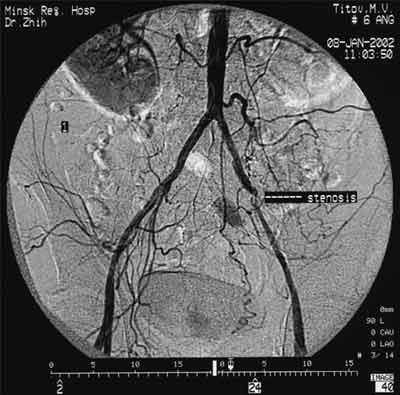

Имплантация артериального стента Белорусского производства.

Рис. 1. Атеросклероз брюшной аорты и ее ветвей.